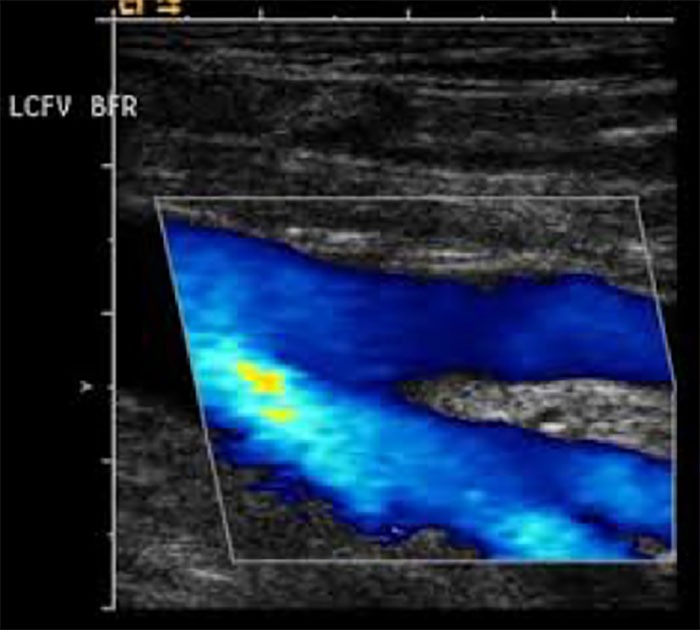

Venous ultrasound is an ultrasound of the venous system in the lower extremities. It is used to diagnose varicose veins, venous insufficiency, and locate a venous thrombus.

Venous ultrasound uses sound waves to produce images of the veins in the body. It is commonly used to search for blood clots, especially in the veins of the leg – a

condition often referred to as deep vein thrombosis. Ultrasound does not use ionizing radiation and has no known harmful effects.